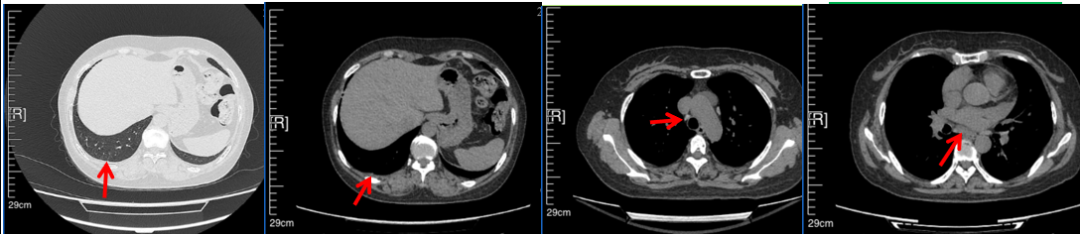

2016年1月复查CT提示支气管截断可见新发小结节,一线治疗采用培美曲塞+DDP方案化疗4周期(培美曲塞3.36,DDP 480mg)。化疗后复查胸部CT:右肺见不规则结节样影,最大层面大小约19mm*8mm,较前比较明显增大,疗效评估PD。2017.3-2017.4予单药多西他赛化疗3周期,疗效评估SD。2018年5月末复查CT提示结节较前增大,评效为PD,2018年6-10月予多西他赛+CBP化疗4周期,疗效评估SD。2022年5月患者出现活动后气短,复查胸部CT示右肺膨胀不良;右侧胸腔积液增多。胸腔积液包埋病理示符合肺腺癌细胞。行NGS基因检测:EML4:exon13-ALK:exon20融合。PD-L1(克隆号22C3)TPS<1%。

2018.07

2022.05

2022.08

2023.05